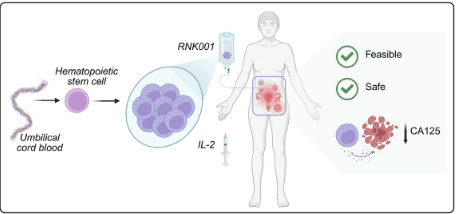

研究人员利用NK细胞产品RNK001安全性的人体研究,RNK001是从脐带血来源的造血干细胞和祖细胞中体外提取的。这项1期INTRO-01试验(NCT03539406)旨在评估腹膜内(IP)输注RNK001在第二次复发时CA125水平升高的(EOC)患者中的可行性、安全性和毒性。

总之,腹膜内输注RNK001治疗复发性EOC是可行的,耐受性良好,在第14天CA125显著降低。一名患者表现出临床和生化反应,疾病在放射学上稳定。

证明IP RNK001输注可有效延长存活时间。一些研究人员已经表明,与静脉注射相比,在携带肿瘤的小鼠中IP输注嵌合抗原受体(CAR)工程T细胞可导致更多的疾病缓解和生存率提高。